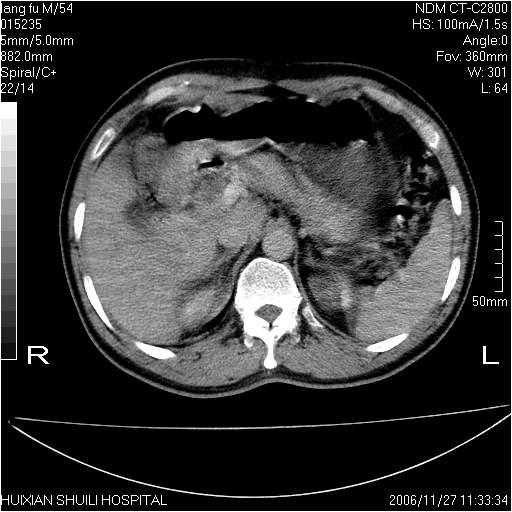

男性,54岁,皮肤黄染,搔痒一周余.b超示肝左叶回声异常.初步诊断1胆总管下段结石2胆囊结石伴慢性胆囊炎请各位战友帮忙看一下肝脏多发低密度如何解释恰当.增强效果不是很好.请大家见谅.

胆总管及肝内胆管扩张,考虑是结石!但,肝内的低密度区增强不明,可能是肝ca,因为肝ca在增强时呈快进快出.另年胆总管扩张原因,可以考虑一下是不是,胆管ca.再次要考虑肝内的低密度是否为海绵状血管瘤所致!

首先,胆总管下端结石梗阻伴肝内胆管扩张可确定。

其次,增强动脉期肝静脉显影,肝实质密度不均。——此为右心功能不全引起肝淤血的表现。

另外,肝八段低密度占位,呈多灶性,考虑肝脓肿或肝癌可能,(图像质量欠佳)建议进一步检查。

既然做了增强,为什么光提供延时期片子,肝动静脉期肝右叶前下段病灶增强如何?另外胆囊壁增厚,欠规整,内密度不均,与肝右叶病灶分界不清,增强表现怎样?肝内胆管轻度扩张,胆总管扩张,但未见明显结石影,也应提供增强早期图像才好鉴别扩张原因。片子较清,但不够完整,暂考虑1.胆囊癌肝局部浸润,或肝癌胆囊侵犯,2.胆总管下端或胰头钩突部占位。总之本人看不明白,请高手画图指示,先谢了!

由于胆囊窝内结构显示不清,肝脏病灶又邻近胆囊窝首先考虑胆囊癌肝受侵犯。而后因肝脏病灶强化有渐进改变,且相邻胆管扩张,故考虑肝胆管细胞癌待排。

左肝胆管细胞癌。

胆总管下端结石。